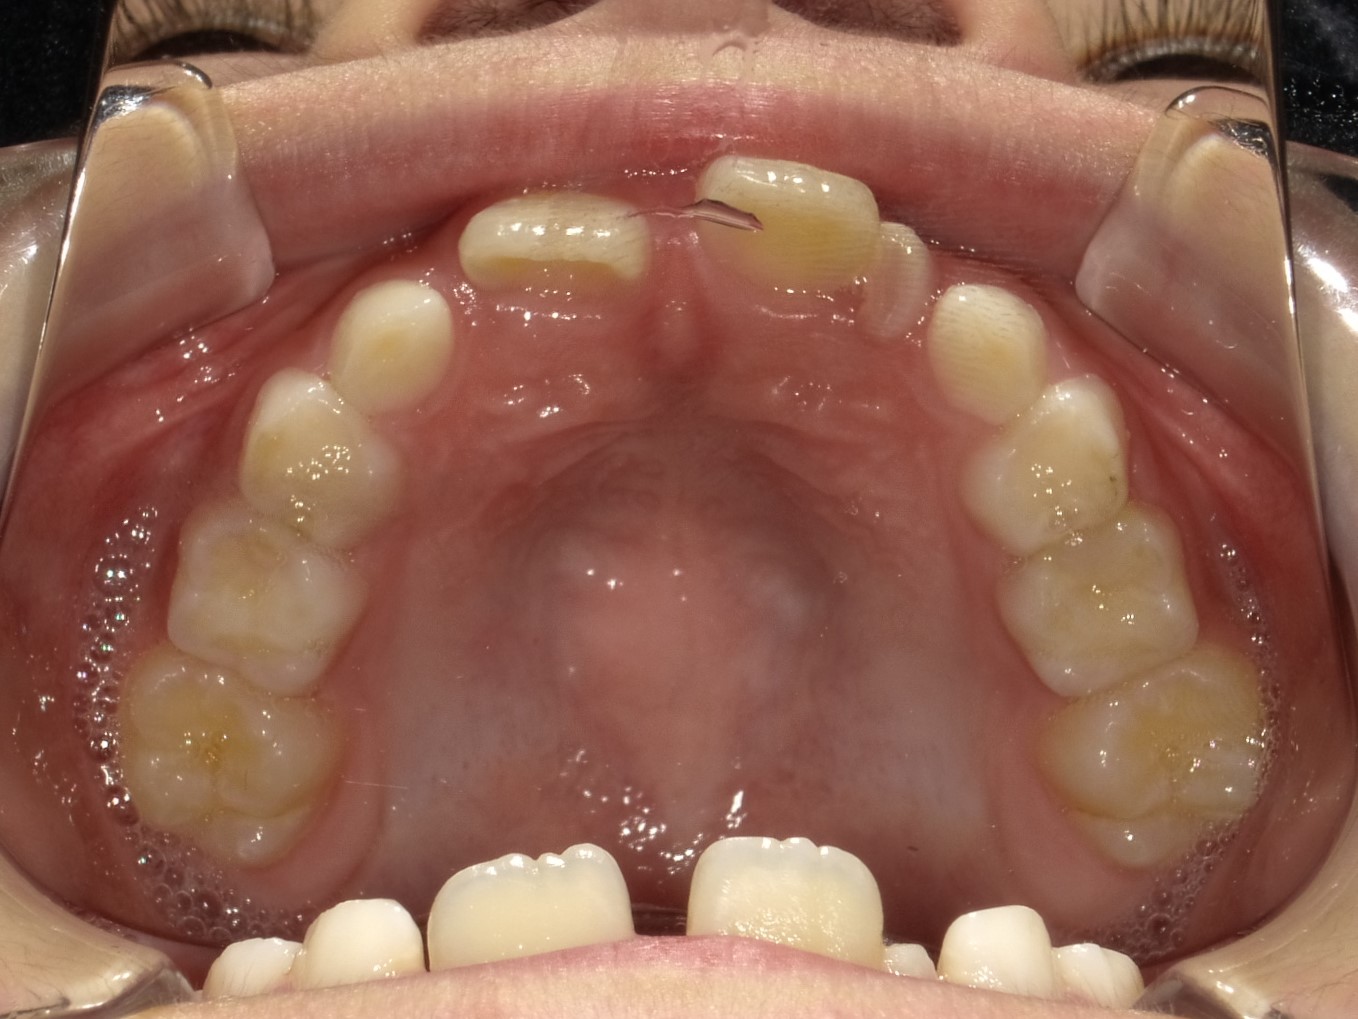

受け口 8歳 男の子 インビザライン

8歳の男の子です。

透明のマウスピース矯正(インビザライン)を用いて治療をしました。

装置が何度か壊れたりトラブルもありましたが、交換頻度を変えながらなんとかここまでキレイになりました!

ゴムの使用も頑張ってくれたのでとてもきれいです!お母さんも非常に気さくな方で楽しく診療できました!

• 治療前

治療前

• 治療後

治療後

インビザラインファースト使用

担当医 堀江将史

治療期間、回数 1年6ヶ月 14回